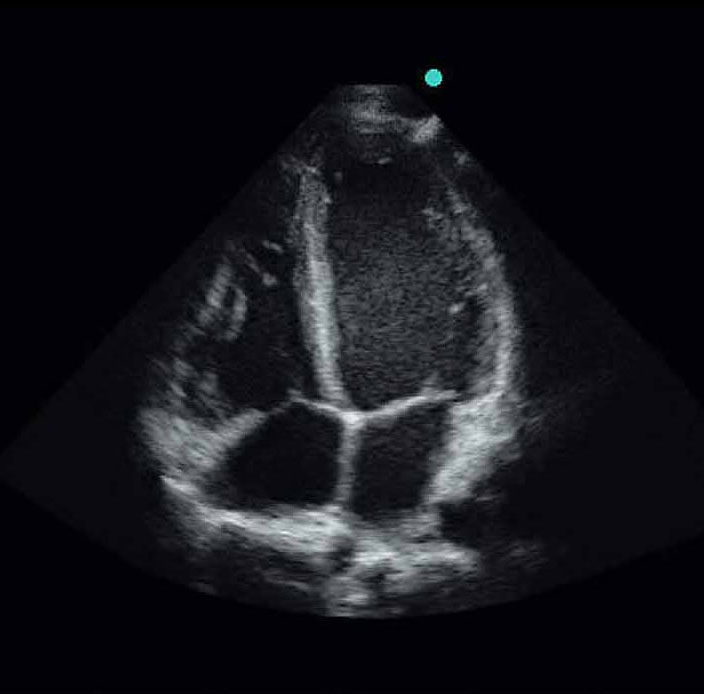

心臓病学1画像